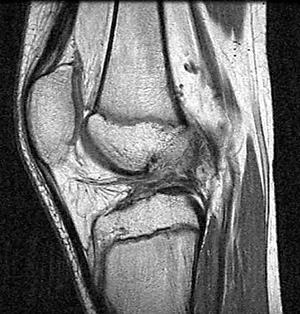

La resonancia magnética es el examen de elección para el diagnóstico de lesión de LCA, sin embargo presenta mayor porcentaje de errores diagnósticos en este grupo de pacientes. Se ha reportado tasas de diagnóstico incorrecto en preadolescentes entre el 36% a 73%. (3, 4) Kocher et al (5) reportó que la sensibilidad diagnóstica para resonancia magnética en niños y adolescentes era de 72%, con especificidad de 93,5%. No encontró diferencia con el diagnóstico clínico, cuya sensibilidad fue de 71,2% con especificidad de 91,5%. Las principales discordancias se encontraron en lesión de menisco externo. Observó además que los pacientes menores de 12 años, presentaban menor sensibilidad y especificidad (61,7%; 90,2%) que los pacientes entre 12 y 16 años (95,5%; 78,2%) (Fig. 1).

Figura 1: Resonancia magnética corte sagital T1, se observa lesión completa de LCA en pacientes de 13 años.